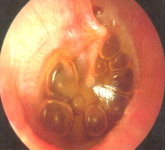

Otitis media with effusion

Otoscopy of otitis media with effusion, showing air fluid levels or bubbles, with normal tympanic membrane landmarks

From the personal collection of Dr Armengol